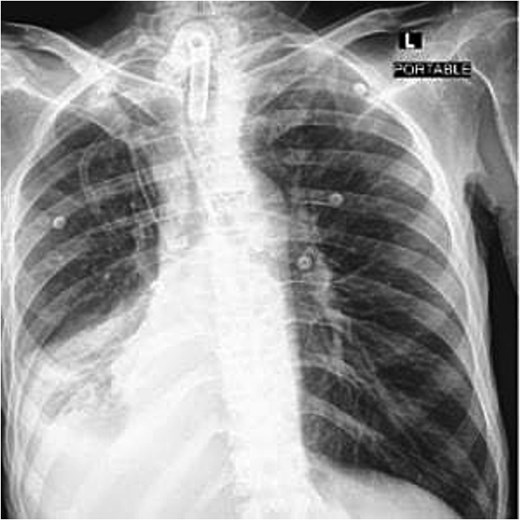

A 40-year-old male who is known to have amyotrophic lateral sclerosis was admitted to the intensive care unit for ventilatory support. He underwent surgical tracheostomy for long-term mechanical ventilation dependence, a double-lumen tracheostomy tube with an internal diameter of 8 mm and a maximum cuff pressure of 25.4 mm was inserted, post-operative chest X-ray confirmed tube placement (Fig. 1). Six months later, the otolaryngologist on-call was consulted regarding ventilation leak that was evident in the ventilator. Flexible endoscopy through the stoma revealed a significantly dilated trachea with a posterior groove. The tube was changed to size 7 with an extended distal length of 49 mm to bypass the dilated segment. A temporary improvement was noted; however, the leak was noted again, with an inspiratory tidal volume of 800, and an expiratory volume of 135, the cuff pressure was gradually elevated to overcome the leak reaching a maximum of 40 mmHg, with the cuff seen over-inflated in routine supine chest X-ray (Fig. 2). Multiple tube obstruction events happened later, which required rigid bronchoscopy examination under general anesthesia to assess and relieve the obstruction. Intraoperative examination revealed that the obstruction was caused by a large dry blood clot, withdrawal of the tube to examine the trachea further revealed a large posterior tracheal wall defect with exposed thoracic vertebrae. The patient underwent a subsequent contrast-enhanced computed tomography scan (CECT) of the neck and chest which confirmed the intraoperative findings (Fig. 3). The leak was not improving by increasing cuff pressure, consequently, the decision was made to use an armored endotracheal tube size 8 at a lip level of 13 to bypass the defect. This has slightly improved the oxygenation and ventilation of the patient, but it did not eliminate the leak. The general poor health of the patient along with his do-not-resuscitate (DNR) status has led to deterring the decision of surgical tracheal wall repair. The patient was further diagnosed with sepsis due to multiple infection sources including his long-term suprapubic urinary catheter, he eventually had a cardiopulmonary collapse a few weeks later and passed away.

Post-operative frontal portable chest radiograph showing a tracheostomy tube in position above the carina.